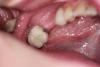

ВИТА Опубликовано 22 августа, 2012 Автор Поделиться Опубликовано 22 августа, 2012 с другой стороны - так Ссылка на комментарий

DShu Опубликовано 23 августа, 2012 Поделиться Опубликовано 23 августа, 2012 с другой стороны - такВ области мезиального импланта расщепление вижу, у дистального нет. Если бы там было расщепление, имплант бы полностью был окружен своей костью, а у вас вестибулярка все равно оголена получилась.И я все таки сторонник фиксировать мембрану, чтобы обеспечить полную иммобилизацию материала. В вашем случае есть риск его сползания.Я бы сделал тут однозначно блок, или импланты+биоос+цитопласт (или титановая мембрана) Ссылка на комментарий

carloss Опубликовано 23 августа, 2012 Поделиться Опубликовано 23 августа, 2012 (изменено) Тоже поддержку что расщепления здесь и не было.Ситуация еще хуже чем в теме "расщепление по карлосу" которое представил биер.Не хватает горизонтального пропила внизу что как раз и дало бы почву для сплита. Опять же вы просто вписали эти имплантаты в то что было и сверху просыпались.Блоков не нужно бояться. Если их делать много и часто то результат вас будет так радовать, что расщепление вам делать уже не захочется. Без обид. http://s61.radikal.ru/i173/1208/96/e3adbd23dfeb.jpg http://s017.radikal.ru/i410/1208/ce/edab2b6855d4.jpg толщина кости вестибулярно в области 35, на фотке с дыркой от 2-х мм пилота и с имплантом одинакова.. соответственно расщепление произошло.. при том, что не было не только нижнего горизонтального, но и вертикальных распилов http://s017.radikal.ru/i443/1208/71/10d1b9973b69.jpgно в любом случае под мембрану(опять же 2 слоя) обязательно аутокость + биоосс для большего объёма.. это мой протокол http://s017.radikal.ru/i425/1208/e3/a95a0270afe4.jpg да.. 34 медиальная консоль)) Изменено 23 августа, 2012 пользователем carloss 1 Ссылка на комментарий